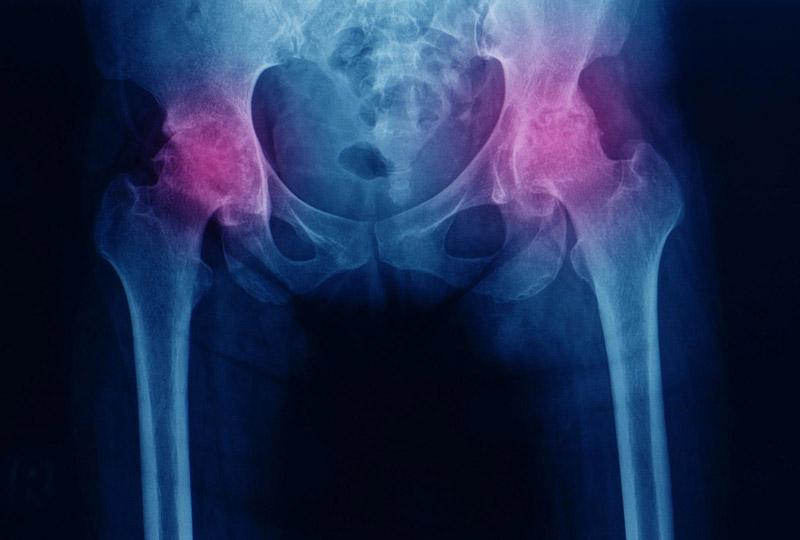

Các kỹ thuật chẩn đoán hình ảnh X quang viêm khớp háng giúp xác định chính xác nguyên nhân, mức độ tổn thương của khớp háng:

Chụp X-quang: Đây là phương pháp phổ biến để chẩn đoán viêm khớp háng, giúp quan sát:

Khe khớp giữa chỏm xương đùi và ổ cối: Nếu khe khớp hẹp hoặc không còn, cho thấy sụn khớp đã bị tổn thương hay mất đi.

Gai xương: Sự xuất hiện của gai xương là dấu hiệu của quá trình thoái hóa khớp, lão hóa.